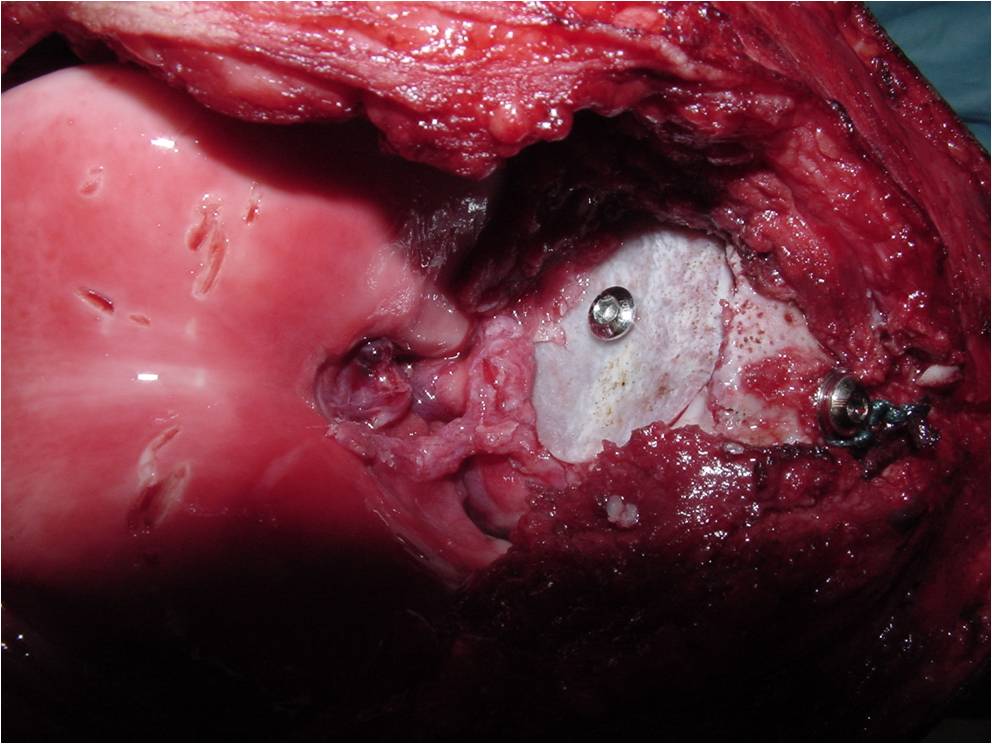

- Treatment of a Chondroblastoma of Proximal Humerus with Intralesional Curettage Resection, Cryosurgery and Bone Grafting

- intralesional curettage resection and bone grafting most common treatment

- Cement and internal fixation may also be used to fill the defect after removal for selected patients

- Local adjuvants such as cryosurgery (liquid nitrogen application) may be considered to decrease the risk of local recurrence